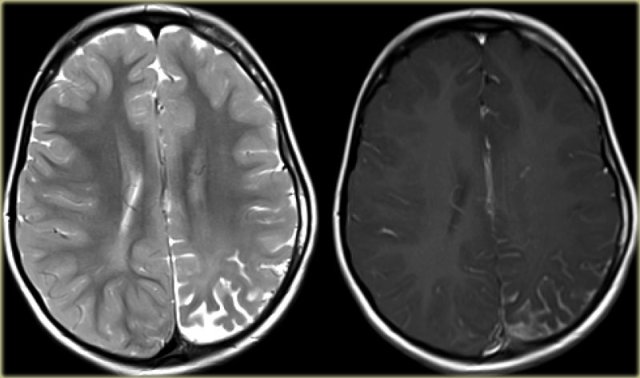

The coronal T2WI and FLAIR images show right-sided mesial temporal sclerosis.

Notice the volume loss, which indicates atrophy and causes secondary enlargement of the temporal horn of the lateral ventricle.

The high signal in the hippocamous reflects gliosis.

The images show mesial temporal sclerosis with a hyperintense and shrunken hippocampus (red arrows), and secondary enlargement of the left temporal horn of the left laterale ventricle.

Also notice associated subcortical hyperintensity in the left temporal lobe indicating focal cortical dysplasia.

35-year-old patient with refractory temporal lobe epilepsy.

MR shows subtle hyperintensity of the left hippocampus on the axial FLAIR (blue arrow) and atrophy of the left hippocampus on coronal images (yellow arrow).

The patient was succesfully treated with amygdalo-hippocampectomy on the left.